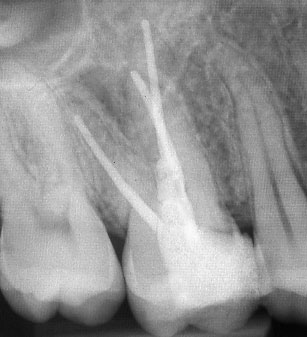

При наличие на огнище на възпаление около корените на зъба добре проведеното лечение води до изчезване на изменението. На снимката долу едва една седмица след пролекуване на каналите се наблюдава известна редукция на патологичния процес. За период от 6 месеца до 2 години е възможно да се наблюдава пълен оздравителен процес.

Понякога е налице патологичен процес около апекса на зъба, който налага да се проведе допълнителна хирургична намеса с цел отстраняване на лезията.